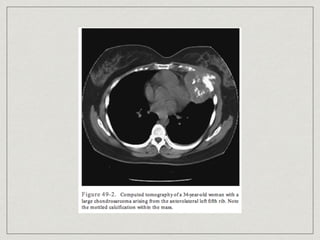

Chondrosarcoma

most common primary chest wall bone neoplasm

60% arises in costochondral arches or sternum

30-40 years old

cause is unknown

slow enlarging mass become painful

lobulated mass arising in medullary portion with

destruction of cortex and mineralization of tumor

matrix(mottled type of calcification)

treatment is complete resection, 5-yr survival of 64%

Chondrosarcoma most common primarychest wall bone neoplasm 60% arises in costochondral arches or sternum 30-40 years old cause is unknown slow enlarging mass become painful lobulated mass arising in medullary portion with destruction of cortex and mineralization of tumor matrix(mottled type of calcification) treatment is complete resection, 5-yr survival of 64%